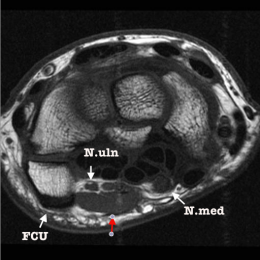

A à D : Coupes axiales du poignet T2 et T1 et coupe sagittale Para-médiane radiale :  formation musculaire accessoire, s'étendant depuis le niveau de la partie distale du radius, jusqu'à hauteur des carpo-métacarpiennes. Cette formation allongée longitudinalement, est située à la face superficielle du pédicule vasculo-nerveux ulnaire. Pas d'altération de signal du nerf ulnaire ou du nerf médian.

Variante anatomique antérieure - long palmaire ? accessoire du fléchisseur ulnaire du carpe.